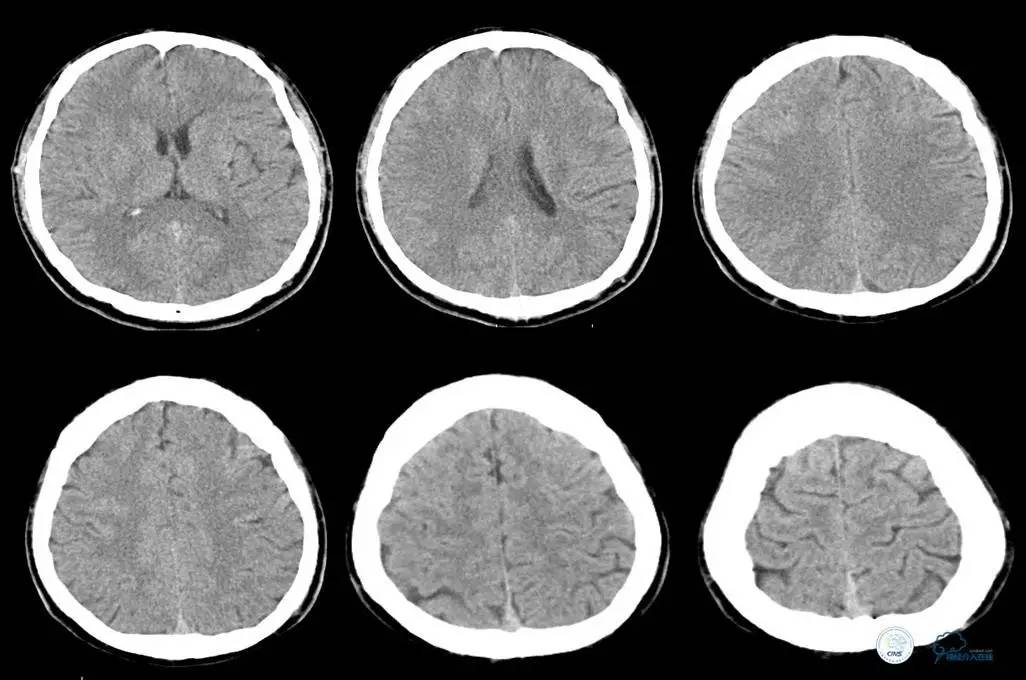

▼头CT

▼心电图:窦性心律,T波异常,心肌缺血改变。

2014年12月15日22时50分

患者言语不清、右侧肢体麻木无力等症状缓解,但四肢末端厥冷。心电监护示,SPO2为99%,P为65次/分,R为18次/分,BP为103/60mmHg。T为35.5℃。

初步诊断为短暂性脑缺血发作。追问患者家属病史,入院前曾有大汗,未进食,低血容量性休克不除外。补液纠正休克。

辅助检查:头CT未见异常。